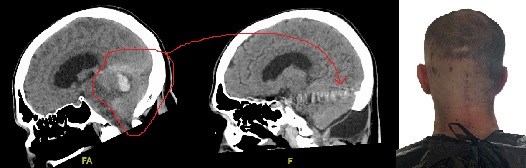

My name is Damian Toohey and I am a stroke survivor. A stroke occurs to an Australian every 11 minutes and while my experience can be described as a stroke, I now tend to think of it as a TBI (Traumatic Brain Injury) as I can honestly say that someone literally cracked my head open and incised my throat. As you read my story, keep in mind that I literally have “rocks in my head” as well, at least the materials used in the endovascular embolisation which could be described as a glue or putty. Knowing if there are other items (such coils and micro-balloons) as well is unclear and something that I am still processing through. Essentially, I just can’t go anywhere and have an MRI of my brain because they want to know these sorts of details.

Here is what I have been able to gather. I experienced a brain bleed resulting from a ruptured dural arteriovenous fistula (DAVF) which is very rare, occurring in a small percentage of an already quite rare condition. A DAVF occurs in fewer than 1 in 100,000 people annually, representing about 10-15% of all intracranial vascular malformations, often affecting middle-aged adults.

During my treatment, it was found that I had an acoustic neuroma (vestibular schwannoma). Acoustic neuromas (vestibular schwannomas) are considered rare, affecting about 1 in 100,000 people annually, though this number may rise due to better detection of small, incidental tumors; they are benign tumors on the nerve connecting the inner ear to the brain, making up a small percentage (6-10%) of all brain tumors, but most cases occur sporadically without a clear cause.

From what I understand, my stroke differs from many in that I carry scars, both externally (back of the head and throat) and internally (on the brain). I have been fortunate in my physical healing and my specialist said that one of my challenges is that I look so well. That is my mask, at least from the front. While my hair has grown, some of my scar from the craniotomy (or craniectomy) procedure can still be seen and the hollow, from where bone was permanently removed from my head, can be made out. Each time I place my hand at the back of my head I am constantly reminded of my rite of passage into the experience of stroke. This is my war wound that accompanies my war story about battling stroke. This is my gift that stops me feeling like an imposter.